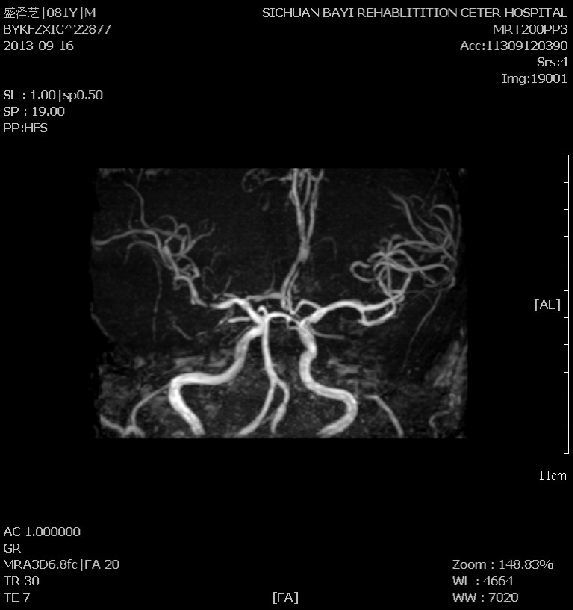

【摘要】:目的探讨MRV对不同时期脑静脉与静脉窦血栓形成(CVST)的诊断价值。方法分析15例CVST患者,同期行MRV和DSA检查,将3D CE-MRV及2D TOF-MRV与DSA进行

磁共振无对比剂血管成像技术(MRA、MRV)的临